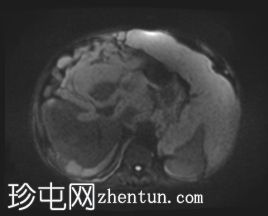

轴向

T2

升结肠壁增厚,尤其前壁,形成肿块,T2信号高,提示其为黏液性肿块。肿块无扩散受限,增强扫描后几乎无强化。

腹腔内可见大量T2信号高、T1信号低至中等的包裹性积液,与腹膜凹陷相符,并导致内脏表面(尤其是肝脏和脾脏)呈扇贝状。这些表现是腹膜假黏液瘤的特征性表现,可能由黏液性肿瘤播散引起。